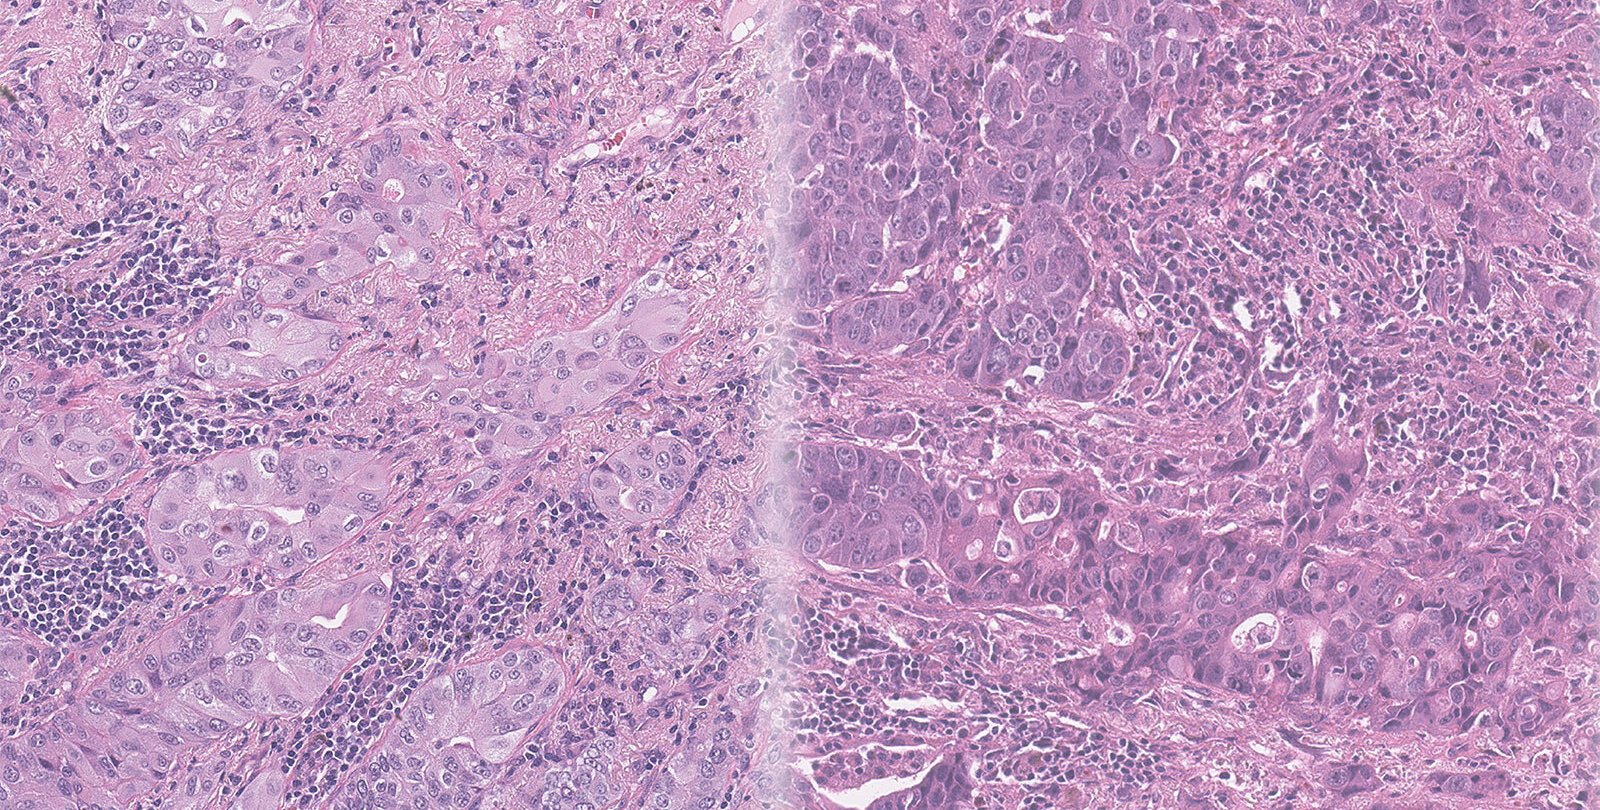

The team worked with data and biopsy images collected from 118 NSCLC patients at Washington University School of Medicine in St. Louis. Typically, a pathologist reviews such images, scouring them for abnormalities within the cells that might suggest the cancer is progressing.

Caltech electrical engineers led by Yang used hundreds of thousands of image tiles pulled from those 118 original biopsy images to train a type of AI program called a deep-learning network. They also provided follow-up data about which patients went on to develop brain metastases within five years of diagnosis and which did not.

"We essentially asked the network to learn from all these images, to pick out some features from the contextual information that could indicate something about a patient's outcome," says graduate student Haowen Zhou, first author of the new paper. Then the network was given 40 additional biopsy images and asked to determine whether the patients had gone on to experience brain metastases.